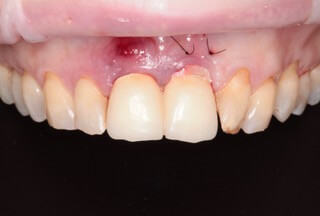

Jediným riešením bola extrakcia obidvoch zubov. Najväčšou obavou zo strany pacientky bola strata obidvoch predných zubov a následného fungovania bez nich pri práci s ľuďmi.

Ideálnym riešením teda bola náhrada zubov implantátmi spolu s nasadením koruniek, a to počas jedného sedenia. V deň konzultácie bol pacientke urobený sken pomocou intraorálneho skeneru 3Shape TRIOS, ktorý nám umožňuje zobraziť 3D simuláciu ústnej dutiny. Pomocou softwaru 3Shape Implant Studio sme spojili dáta z intraorálneho skenu a CBCT, STL a DICOM súbory.

V ďalšom kroku sme virtuálne vložili implantáty v správnej protetickej polohe, navrhli šablónu pre ich zavedenie, namodelovali individuálne abutmenty a korunky. Kompletné dáta sme exportovali pre frézovanie a 3D tlač. V laboratóriu sa pomocou 3D tlačiarne vytlačila chirurgická šablóna, ktorá nám slúži na presné zavedenie implantátov – použili sme implantačný systém Dentium Super Line. Následne boli vyfrézované zirkonové abutmenty a plastové dočasné korunky.

Ukážka - navigovaná chirurgia z praxe